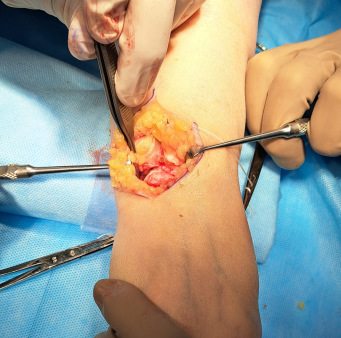

During the operation, conduction anesthesia was used. The patient’s position was supine with the arm on the bedside counter. After preparing the surgical field, a hemostatic pneumatic tourniquet was applied at the level of the middle third of the humerus. Surgical approach to the scaphoid bone was carried out from a 4–5 cm long incision along the anterior surface of the forearm, using the flexor carpi radialis (FCR) as an external landmark. After making the incision, the tendon was moved to the side for exposure of the capsule of the wrist joint and for examination of the articular surfaces of the distal radius and scaphoid bones (Fig. 1). Next, resection of the scaphoid bone was performed. To prevent impingement syndrome, resection of the styloid process of the radius was performed. Then, through an additional dorsal approach 4–5 cm long, the retinaculum extensorum was exposed and the 5th canal of extensors was opened. The extensor tendons of the fifth finger were moved to the side, the wrist capsule was incised along the dorsal radiocarpal ligament (DRC) (Fig. 2), and the distal radius and midcarpal joint were examined to ensure the integrity of the lunate fossa of the radius and capitate bones.

| Fig. 1 Palmar approach | Fig. 2 Dorsal approach to the wrist |